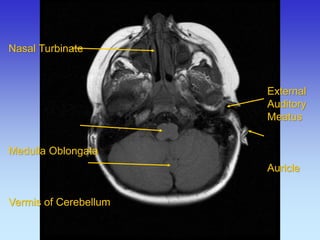

External auditory meatus

Mastoid air cells

Medulla oblangata

Nasal septum

Temporalis m

Trapezius m

Nasal Turbinate Medulla Oblongata Vermis of Cerebellum

External Auditory Meatus Auricle